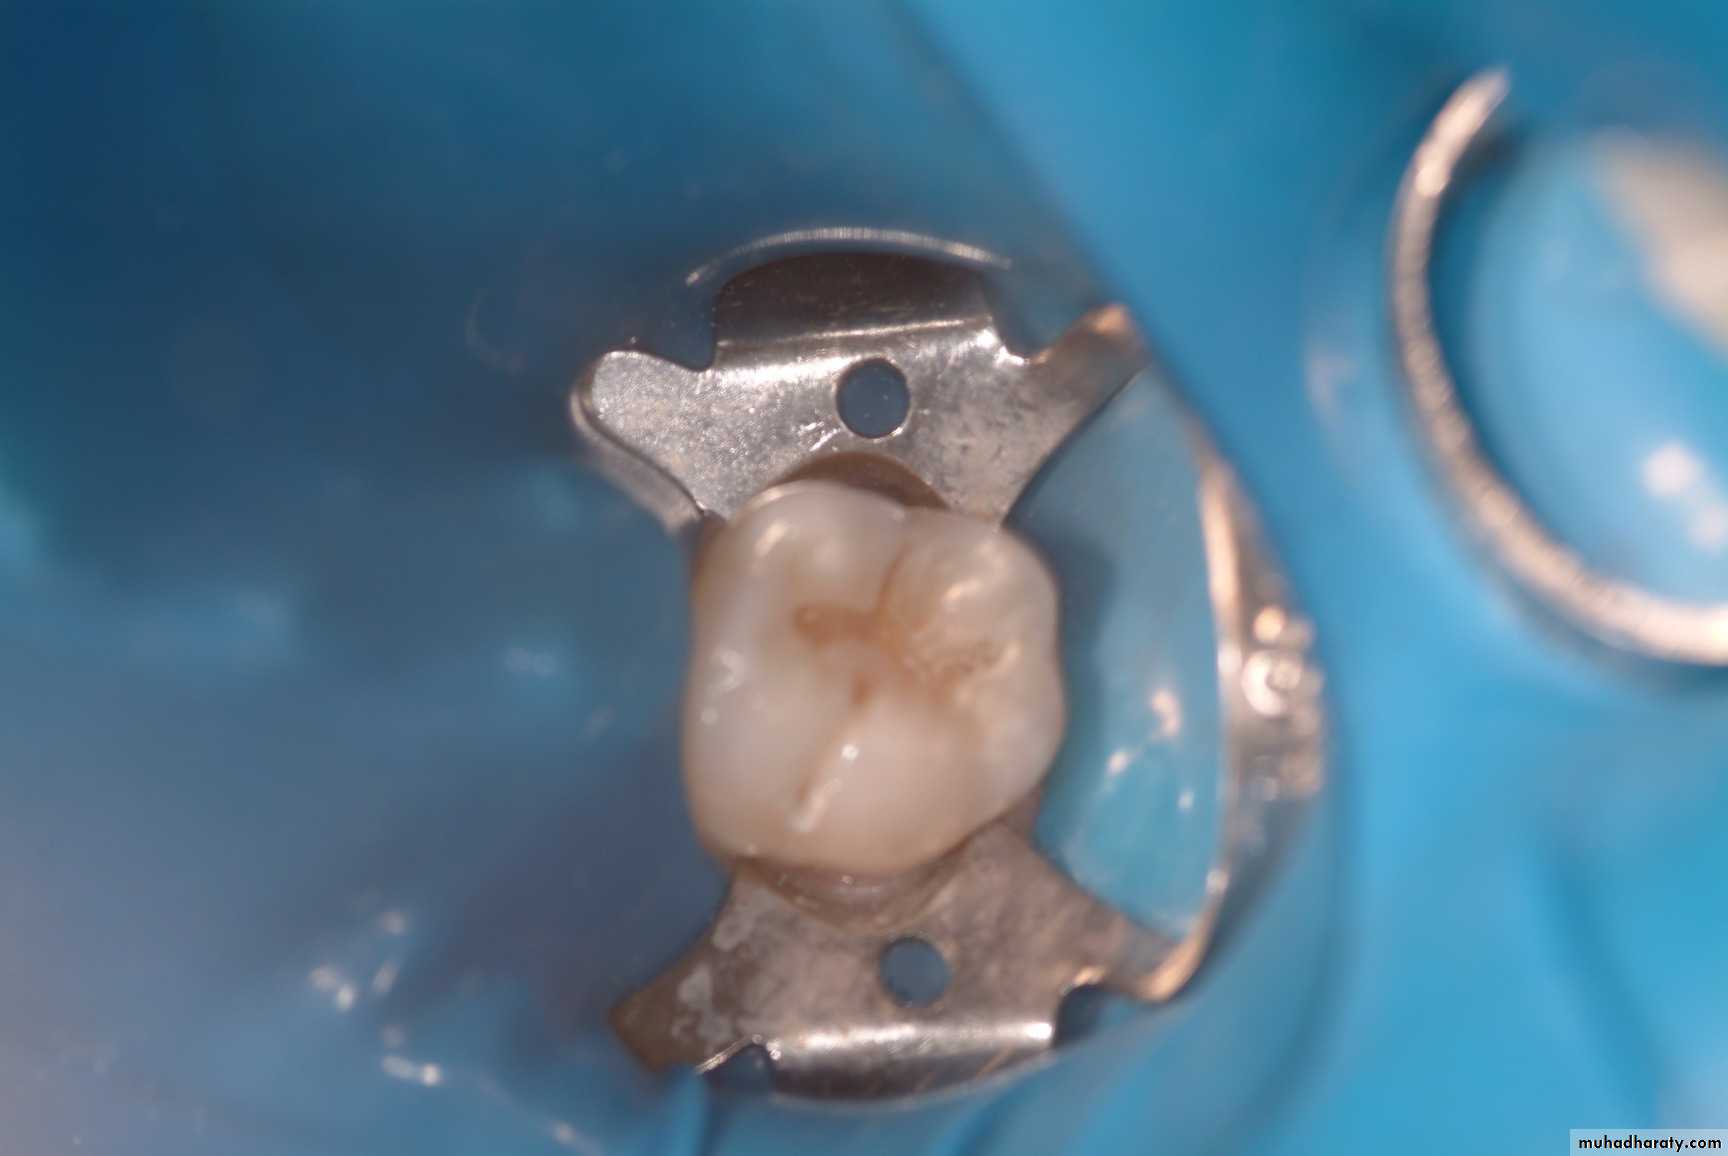

Diagnosis Of Dental Caries

Earliest caries detection, traditionally by use of mirror and light, as well as bitewing radiographs, can now be aided by new innovations in dental magnification and imaging, laser fluorescence and quantitative light-induced fluorescence.

Laser in Conservative Dentistry